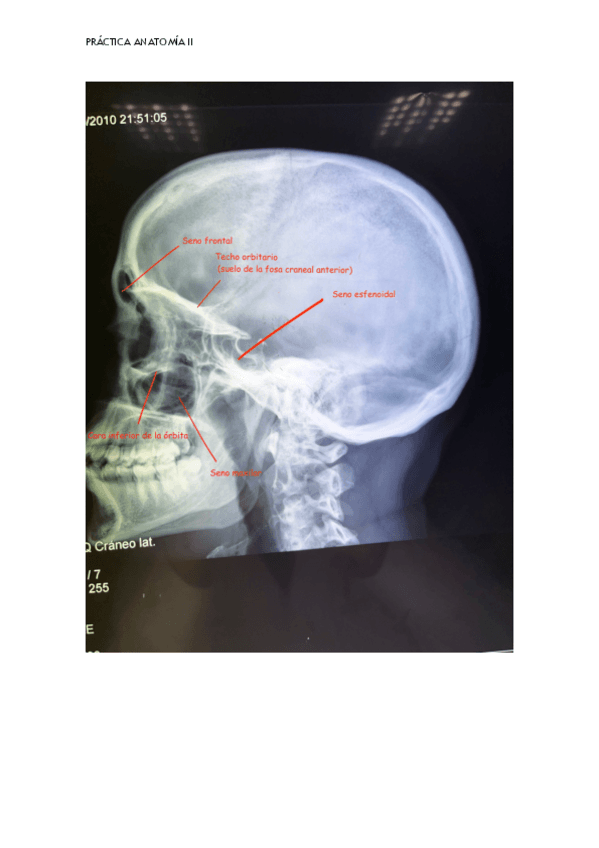

radiologicas-craneo.pdf

Apuntes - radiologicas-craneo.pdf